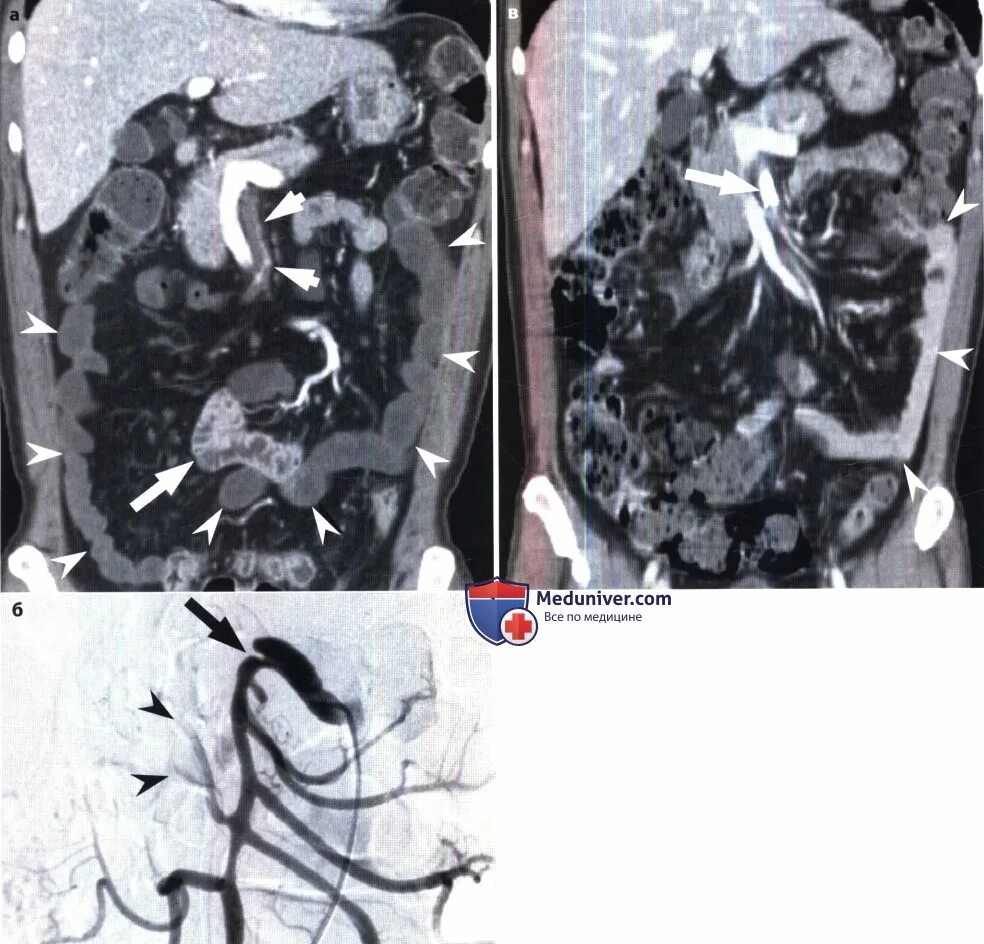

Тромбоз брыжеечной артерии